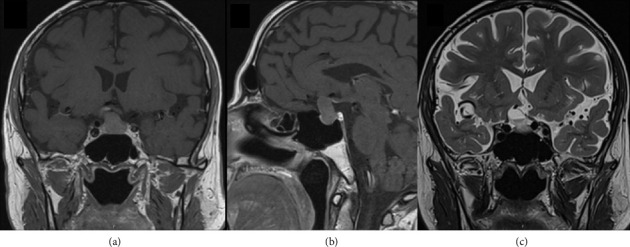

鞍形弓形体病在垂体中的发生极为罕见,文献中仅有少数报道,主要影响免疫功能低下的患者。我们报告一个有趣的情况下,54岁的男子与最初的无症状全垂体功能低下诊断在调查尿石症。头颅CT及MRI显示一大片鞍区病变,初步怀疑为无功能的垂体大腺瘤。经鼻内蝶窦手术,组织病理诊断为垂体刚地弓形虫脓肿。本病例强调,这些类型的感染也可发生在免疫功能正常的患者。

The occurrence of sellar toxoplasmosis in the pituitary gland is exceedingly rare, and only a few reports have been published in the literature, primarily impacting immunocompromised patients. We report an intriguing case of a 54-year-old man with an initial asymptomatic panhypopituitarism diagnosed under investigation for urolithiasis. Cranial CT and MRI revealed a large sellar lesion first suspectable of a nonfunctioning pituitary macroadenoma. An endonasal transsphenoidal surgery was performed, and the histopathological diagnosis was surprisingly a pituitary Toxoplasma gondii abscess. This case highlights that these types of infections can also occur in immunocompetent patients.